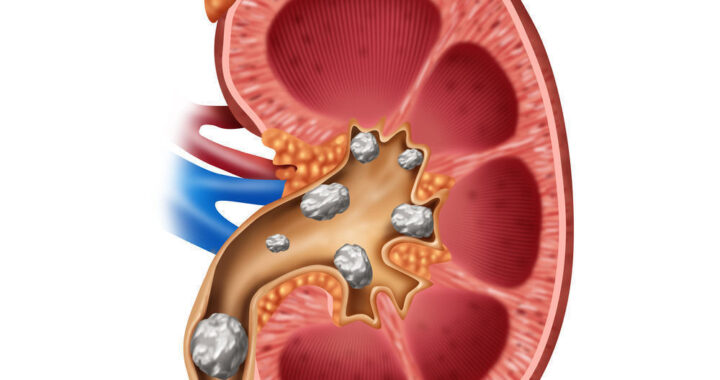

Batu Ginjal dan Dampaknya: Kenali Sebelum Terlambat

Batu ginjal adalah kondisi medis yang terjadi ketika mineral dan garam dalam urin mengkristal dan membentuk massa keras di dalam ginjal. Proses ini biasanya dipicu oleh konsentrasi zat tertentu yang terlalu tinggi dalam urin, seperti kalsium, oksalat, atau asam urat. Ginjal yang berfungsi menyaring limbah dari darah seharusnya menghasilkan urin yang seimbang, namun ketika keseimbangan ini terganggu, kristal dapat terbentuk dan berkembang menjadi batu. Ukuran batu ginjal bervariasi, mulai dari sekecil butiran pasir hingga sebesar bola kecil, dan keberadaannya dapat menyebabkan rasa nyeri yang sangat hebat ketika bergerak melalui saluran kemih.

Penyebab batu ginjal sangat beragam dan sering kali dipengaruhi oleh gaya hidup serta faktor kesehatan tertentu. Kurangnya asupan cairan merupakan salah satu faktor utama, karena urin yang terlalu pekat memudahkan pembentukan kristal. Pola makan yang tinggi garam, protein hewani, dan oksalat juga dapat meningkatkan risiko. Selain itu, kondisi medis seperti obesitas, gangguan metabolisme, infeksi saluran kemih, serta riwayat keluarga dengan batu ginjal turut berperan dalam meningkatkan kemungkinan seseorang mengalami kondisi ini. Beberapa jenis batu ginjal yang umum meliputi batu kalsium, batu asam urat, batu struvit, dan batu sistin, masing-masing dengan karakteristik dan penyebab yang berbeda.

Penanganan batu ginjal tergantung pada ukuran, jenis, dan tingkat keparahannya. Batu kecil biasanya dapat keluar dengan sendirinya melalui urin dengan bantuan konsumsi air yang cukup dan obat pereda nyeri. Namun, untuk batu yang lebih besar atau menyebabkan komplikasi, diperlukan tindakan medis seperti terapi gelombang kejut (ESWL) untuk memecah batu, ureteroskopi untuk mengangkat batu melalui saluran kemih, atau operasi dalam kasus yang lebih serius. Selain itu, dokter juga dapat meresepkan obat-obatan tertentu untuk membantu melarutkan batu atau mencegah pembentukan kembali, tergantung pada jenis batu yang dialami pasien.

Pencegahan batu ginjal sangat penting untuk menghindari kekambuhan, karena kondisi ini cenderung berulang jika tidak ditangani dengan baik. Salah satu langkah paling efektif adalah menjaga asupan cairan dengan minum air putih minimal dua hingga tiga liter per hari agar urin tetap encer. Mengurangi konsumsi garam, membatasi protein hewani, serta menghindari makanan tinggi oksalat seperti bayam dan cokelat juga dapat membantu. Selain itu, menjaga berat badan ideal dan rutin melakukan pemeriksaan kesehatan sangat dianjurkan, terutama bagi individu yang memiliki risiko tinggi. Dengan perubahan gaya hidup yang tepat dan kesadaran akan pentingnya kesehatan ginjal, risiko batu ginjal dapat diminimalkan secara signifikan.